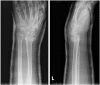

Background: The aim of this study was to compare the functional outcomes and complications of volar and dorsal plating for the management of intra-articular distal radius fractures, with special regard to indications for dorsal plating. Furthermore, we examine the rationale for choosing dorsal plating and its frequency of use.

Methods: Clinical assessments included range of motion measurements at the wrist; grip strength; the Quick Disabilities of the Arm, Shoulder, and Hand score; and the Gartland and Werley score. Clinical results were compared with those achieved using a volarly placed locking plate system. According to Lutsky's plate theory, the rationale for choosing dorsal plating was based on 4 types of pathologic fractures.

Results: Of 112 patients, 38 patients were treated with open reduction internal fixation via a dorsal approach and 68 patients were treated using a volar approach. Except for wrist flexion, there were no other statistical differences in the clinical results between groups for both subjective and objective parameters. There were no statistically significant differences in the complication rates between the volar and dorsal plated groups. One serious complication occurred after volar plating. The most common reason for choosing dorsal plating was irreducible dorsal die-punch fractures.

Conclusions: The treatment of displaced intra-articular distal radius fractures with a dorsally versus a volarly placed interlocking plate system demonstrated similar clinical results. Postoperative complications were not readily observed in the patients treated with a dorsal locking plate. Certain fracture patterns are more appropriately stabilized using a dorsal plate fixation.